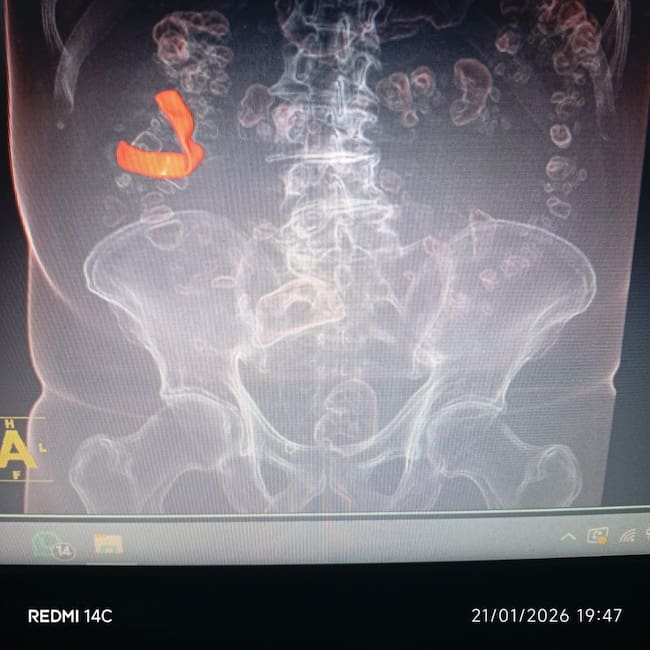

“Durante años acudió a consultas médicas por estos síntomas, pero al ser considerados leves, únicamente se le formulaban medicamentos y reposo”, explicó. Sin embargo, la situación cambió en diciembre de 2025, cuando, tras la realización de exámenes de rutina, una radiografía evidenció la presencia de un cuerpo extraño en su organismo.

Posteriormente, mediante estudios imagenológicos adicionales como ecografías, se logró confirmar la existencia del elemento, el cual, según indicó la defensa, se presume sería una gasa quirúrgica o compresas que habría quedado en el cuerpo durante la intervención realizada en 2018.